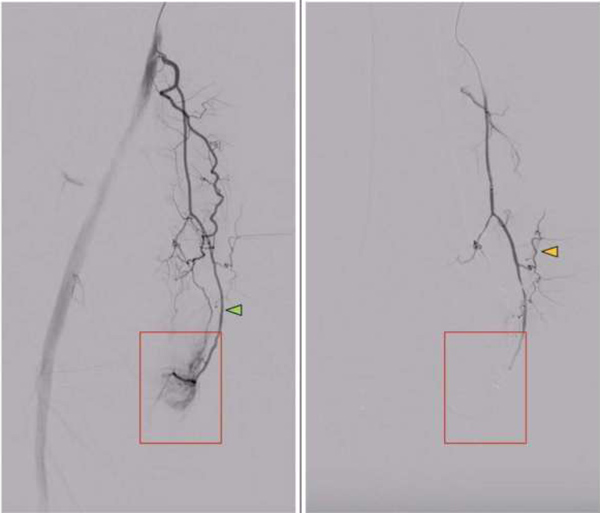

Minimally invasive procedure relieves knee arthritis Medical Express - December 3, 2024

An interventional radiologist injects small particles into selected branches that correspond to the site of knee pain to block blood flow to that area. Embolization of the abnormal blood vessels helps to disrupt the cycle of inflammation, cartilage destruction and sensory nerve growth that characterizes osteoarthritis.